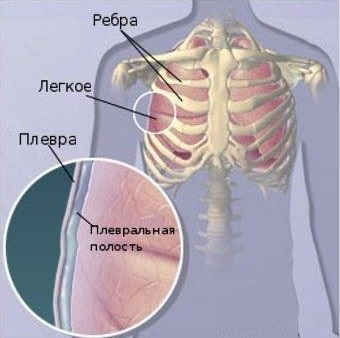

Reakcióvázlat anatómiája a mellhártya és a tüdő arányok.

Tünetek általában kimutatható nézve a mellkas és a tüdő hallgatózás, csökken a lag légzésben és néhány vizuális aszimmetria az érintett része a mellkas, amelyek mellett a gyengülő vagy teljes hiánya puding helye túlzott felhalmozódása váladék.

Ha elkezd megkopogtat, azaz megérinti, a mellkas, a váladék fogja azonosítani ugyanebben hangot a combot. Utolsó nevezett hülye vagy combcsont és fontos, megbízható diagnosztikai jele tüdőömlenyek, amelyen keresztül lehet azonnal meghatározza a szint körülbelül váladékos folyadékot.

Jelenlétének igazolására a folyadékgyülem a mellhártya üregbe, most kötelezően alkalmazandó röntgen vizsgálata: a radiológiai vizsgálata blackout megfelelő területen váladék.